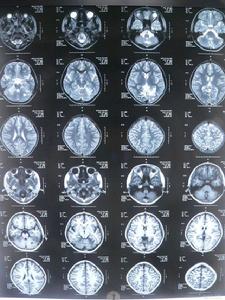

(4)輔助檢查:①X片可見脊柱和骨骼畸形;MRI可見脊髓變細;②心電圖常見T波倒置、心律失常和傳導阻滯,超聲心動圖示心室肥大,視覺誘發電位波幅下降;③DNA分析FRDA基因18號內含子GAA大於66次重複。

遺傳性共濟失調2、Friedreich型共濟失調(FRDA)X片可見脊柱和骨骼畸形;MRI可見脊髓變細;心電圖常見T波倒置、心律失常和傳導阻滯,超聲心動圖示心室肥大,視覺誘發電位波幅下降。